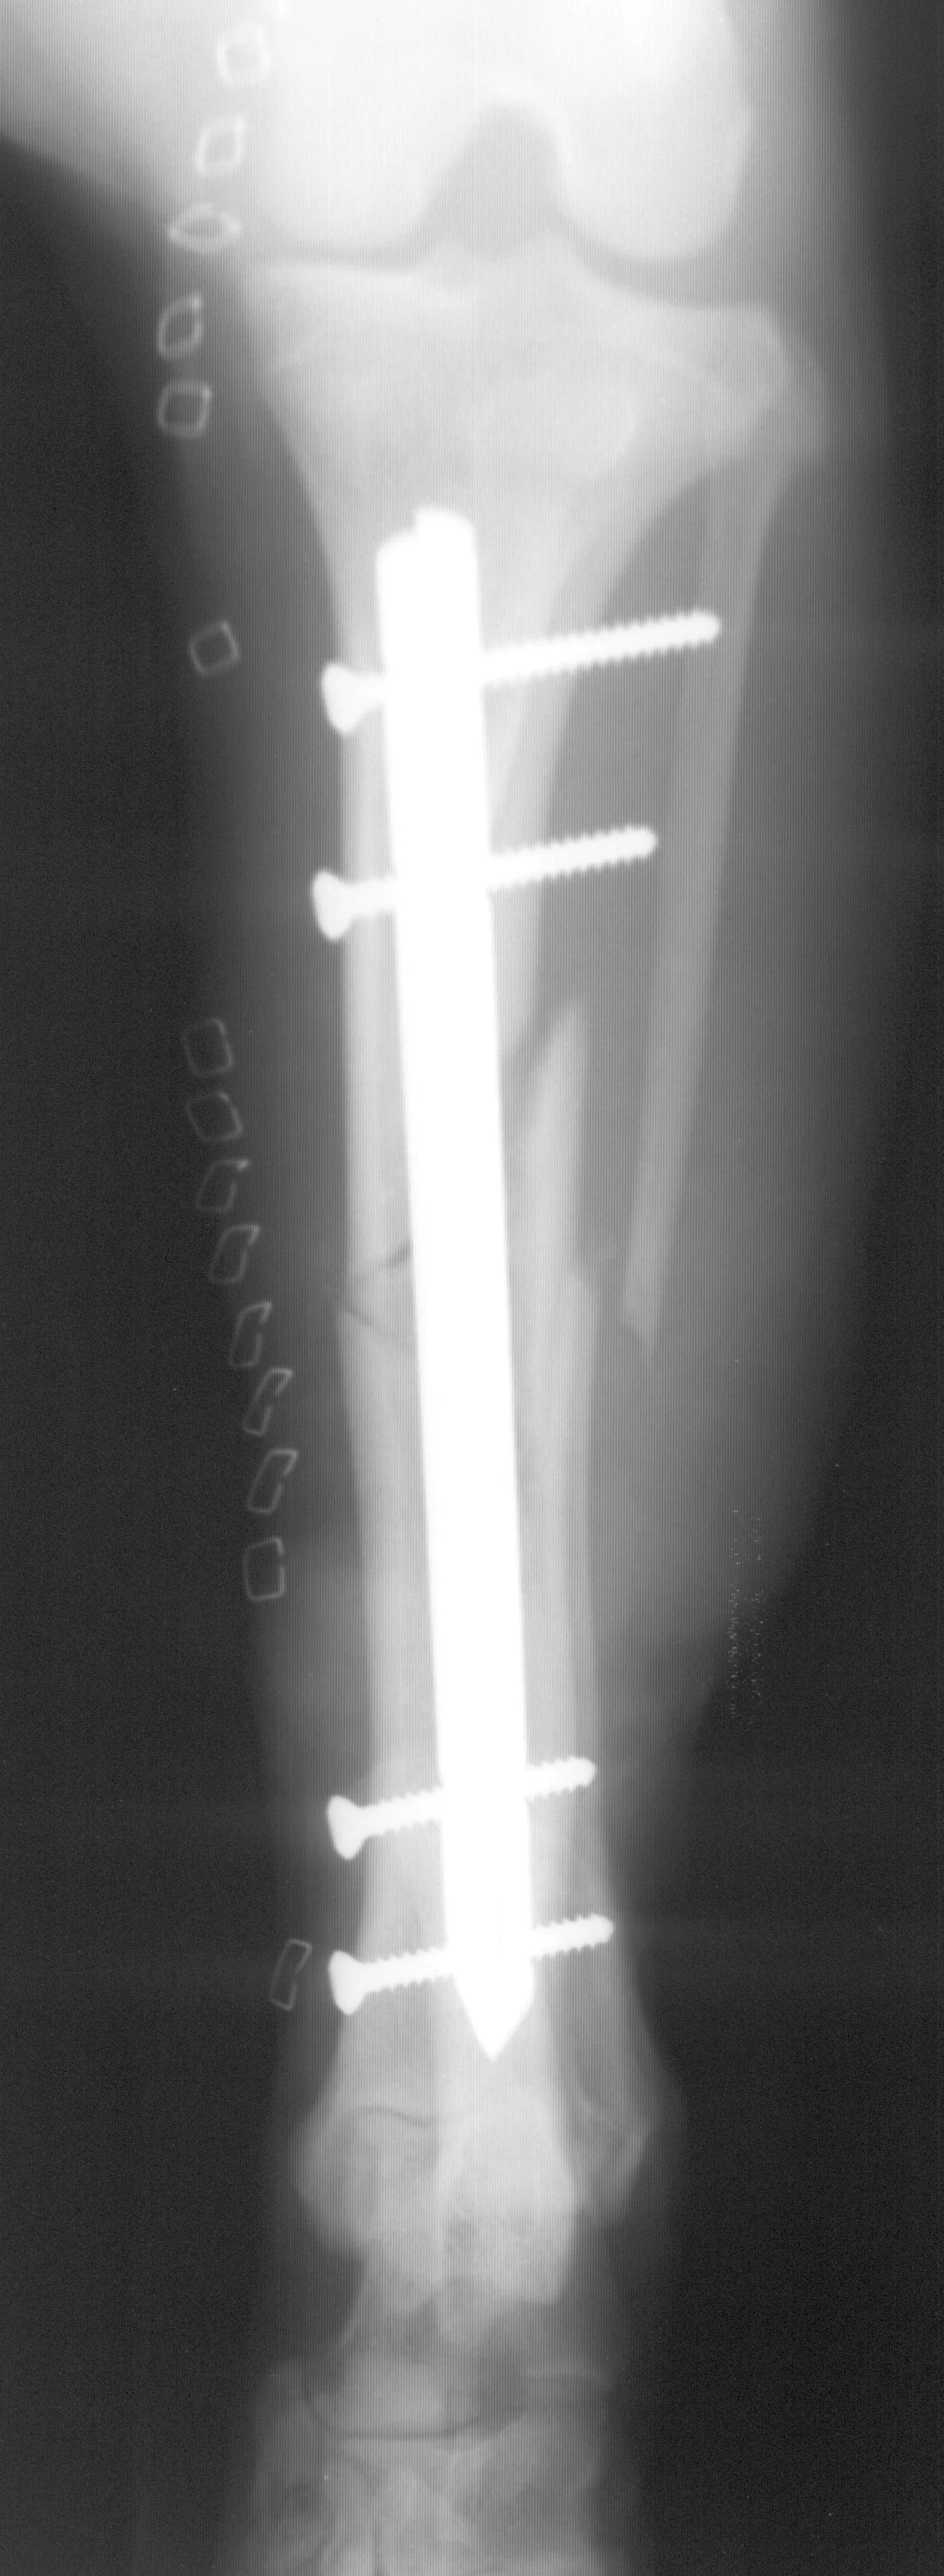

Fractures managed using interlocking nails and biologic technique develop extensive bridging callus and early return to function. A minimally invasive surgical approach (note the surgical skin staples) was made to this fracture to minimize disruption of the blood supply to the bone fragment. The fracture fragments quickly become incorporated in the callus if soft tissue attachments can be maintained.

Healing of the comminuted tibial fracture shown in Figures 2A and 2B after stabilization using an interlocking nail system. This fracture reached bony union in 8 weeks.